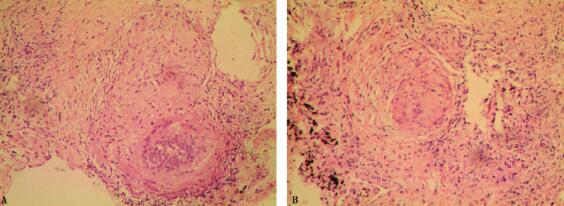

7.胸部高分辨CT(2008年12月25日):双肺纹理增多紊乱,双肺弥漫磨玻璃、斑片、结节影,密度不均匀,边界欠清,部分沿支气管血管束分布,纵隔内见多个增大淋巴结,双侧肺门正常,双侧胸腔内未见积液(图1)。

图1

1.胸部高分辨CT提示病变累及周围肺间质、肺泡腔、所属淋巴管、支气管壁及淋巴结。分析如下:①疾病累及肺泡腔为主,如肺泡蛋白沉积症(PAP)、特殊病原体感染(包括结核菌、真菌等)等;②源于淋巴组织疾病,如结节病、肿瘤(包括淋巴系统肿瘤)等;③风湿性疾病,如肉芽肿性疾病、血管炎等;④职业相关疾病,如铍肺等。但上述疾病单纯依靠胸部CT难以鉴别,需要取得组织病理,明确诊断。

结节病的胸部CT,尤其是HRCT的影像学,典型表现是以双侧肺门、纵隔淋巴结对称性肿大为特征,肺内改变早期为肺泡炎表现,继而发展为肺间质浸润,以及晚期肺间质纤维化。而不典型胸部CT可表现如下:支气管狭窄或压迫,甚至造成肺不张,特别是右肺中叶;肺内孤立阴影;空洞病变;单侧或双侧肺实变;双肺粟粒样结节;胸腔积液、液气胸;单侧纵隔和(或)肺门淋巴结肿大、双侧肺门淋巴结不对称肿大以及淋巴结钙化等。

HRCT对于评价第Ⅱ、Ⅲ期结节病的肺内活动性炎症和不可逆的肺纤维化有重要意义。通常情况下结节影、磨玻璃影、肺泡实变影均被认为是可用药物治疗逆转的肉芽肿性改变;而蜂窝肺、囊性改变、肺大泡、粗大的小叶间隔影像、肺结构破坏、牵拉性支气管扩张、肺容积减少预示疾病不可逆。本例胸部CT主要表现为双肺内弥漫性片状影、小结节影、腺泡样影,从影像学分析仍以肉芽肿性炎症为主,虽有轻微的牵拉性细支气管扩张,病情仍可逆,预示治疗反应相对较好。但胸部HRCT有轻微的牵拉性细支气管扩张,提示可能存在纤维组织增生,药物治疗后不完全可逆,预计可能遗留纤维瘢痕或支气管扩张。随后的治疗反应充分印证了上述观点。